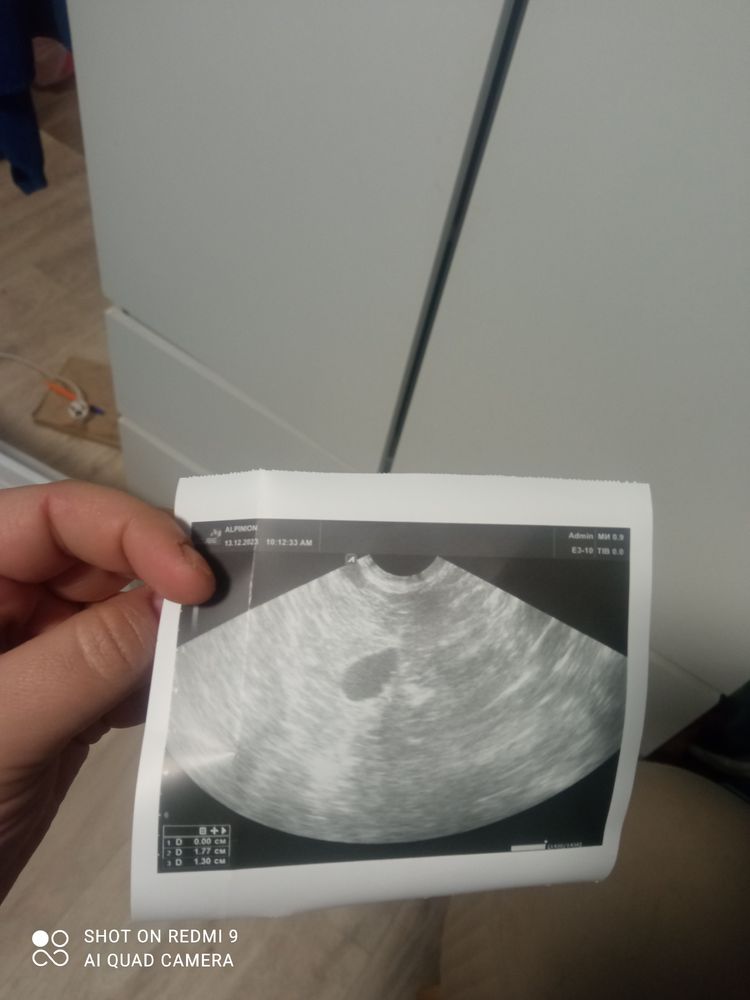

Гинеколог сказала это жидкость рядом с яичниками после внематочной. Так ли это? За день до этого сдавала хчг 0.2 был

Что это может быть ? После внематочной прошёл почти год. Месячных нет